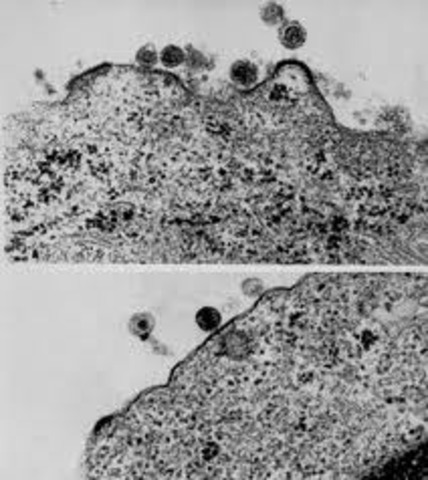

Testing in animals start, but they use chimps or gorillas. When they do the testing on the animals they inject them with HIV. And do many drug testing on them. Also at this time information leads to that haitians are starting to get the disease. The CDC finds out what the disease is doing to break down the body, which is that something is gobbling up the T cells.